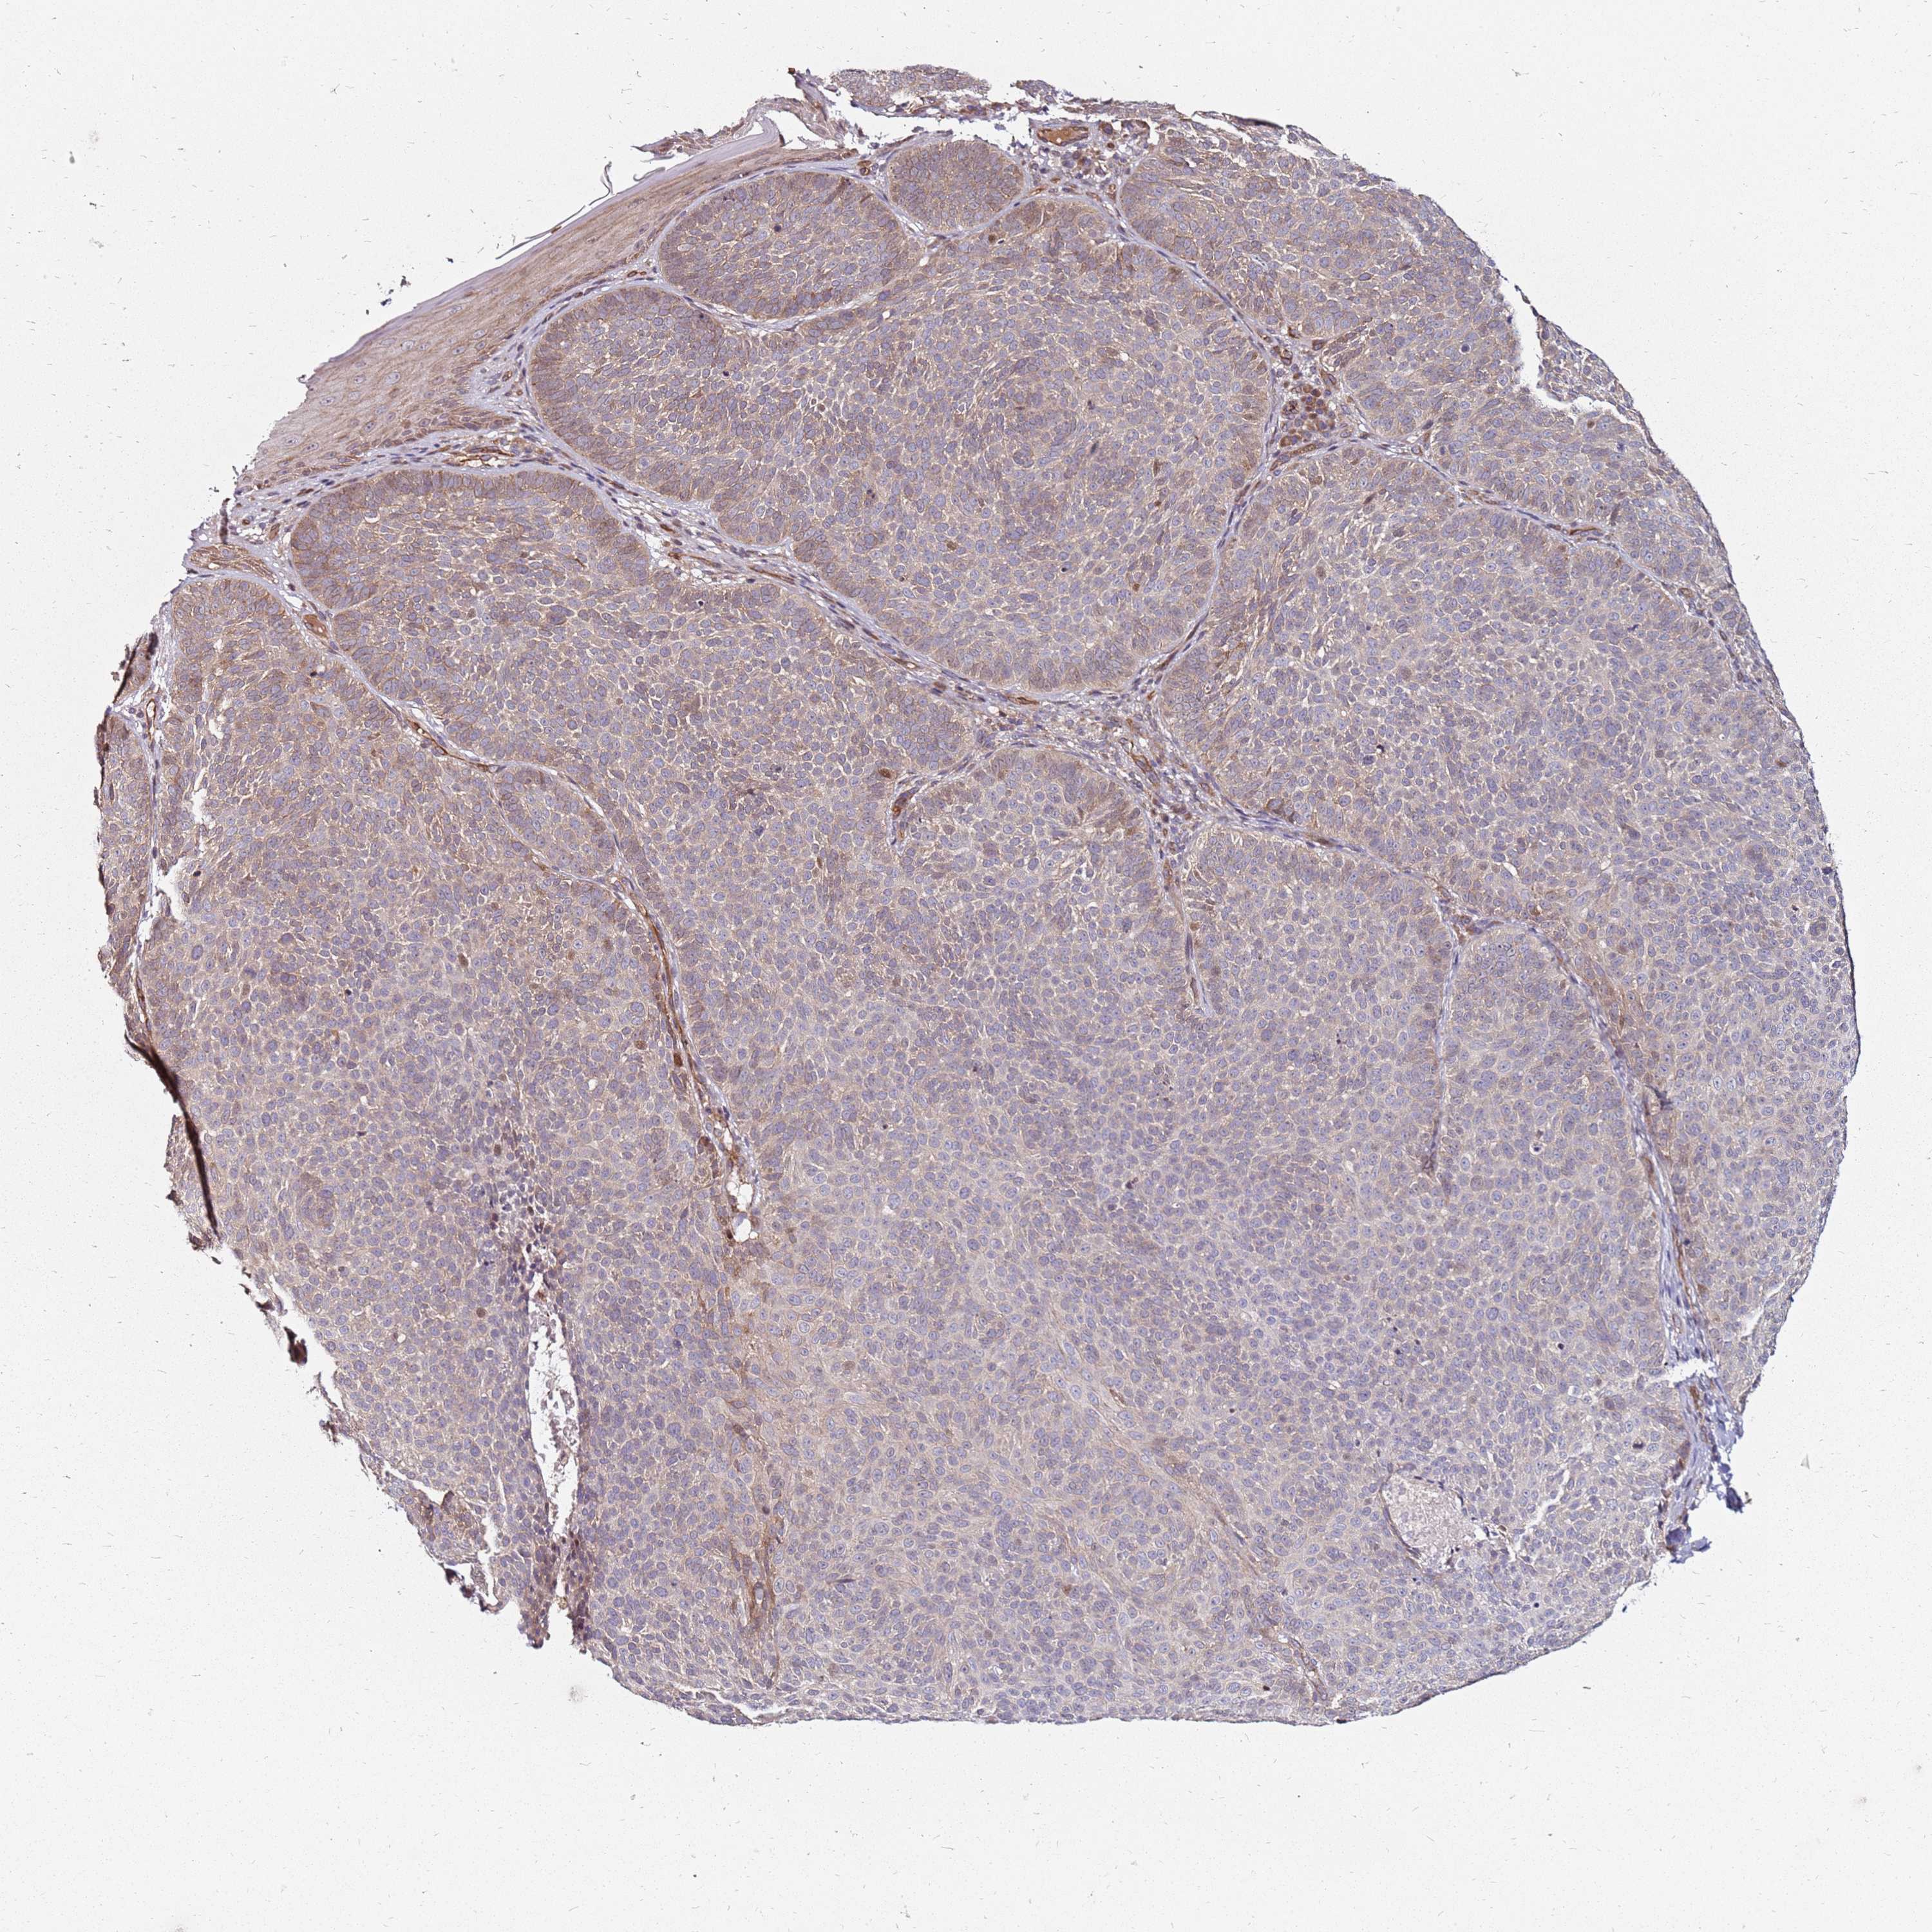

SKIN CANCER - Protein expressioni

A mouse-over function shows sample information and annotation data. Click on an image to view it in a full screen mode. Samples can be filtered based on level of antibody staining by selecting one or several of the following categories: high, medium, low and not detected. The assay and annotation is described here.

Each image is clickable and will lead to virtual microscopy that enables deeper exploration of all samples and also displays staining intensity scores, fraction scores and subcellular localization as well as patient and tissue information for each sample.

Antibody HPA045781

Basal cell carcinoma